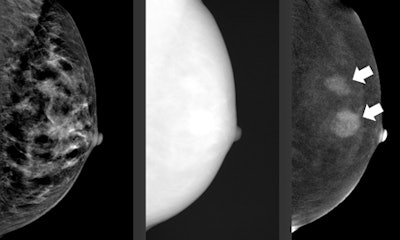

Radiologists are always on the lookout for the latest and greatest technology, and this is particularly true in breast imaging, because the primary modality, mammography, is not exactly perfect. Rapid progress in both CT and MRI are being made in this field.

"There is a general consensus that the sensitivity and specificity of screening mammography is unsatisfactorily low," Dr. Willi Kalender, PhD, chairman of the Institute of Medical Physics at the University of Erlangen in Germany, told ECR Today. "MRI offers much higher values but lacks imaging of microcalcifications, is more costly, and [is] time-consuming."

As an alternative, he suggests dedicated breast CT, first described in detail in 2012. The goal of breast CT is to offer high-resolution CT imaging at a very low dose and increased sensitivity and specificity. CT can offer superposition-free imaging with a very high spatial resolution of 100 µm or better in all three spatial dimensions, dose levels low enough to conform with mammographic screening regulations, dynamic imaging with contrast medium application when indicated, and integrated biopsy capabilities, he explained.

He plans to provide an overview for both dedicated and general radiologists of the current most promising developments, including contrast-enhanced mammography, also called contrast-enhanced spectral mammography (CESM), which became commercially available in 2011. It uses an iodine-based contrast agent and a dual-energy technique to increase the diagnostic accuracy of mammography.

"In recent years, many studies have shown that CESM is consistently superior to full-field digital mammography [FFDM] in breast cancer detection and able to achieve results similar to breast MRI, which is still considered to be the most accurate breast cancer detection modality," Lobbes noted.

CESM could easily be implemented in everyday clinical practice, but there are some disadvantages, such as the use of iodine-based contrast agents and the 80% increase in radiation dose. Also, CESM doesn't have proper indications, he added.